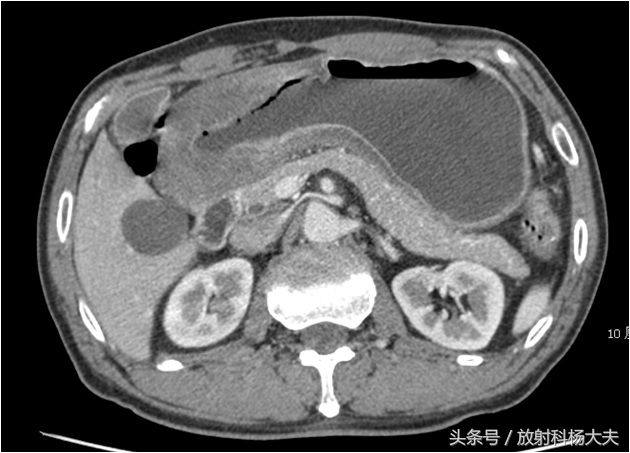

CT图:胃窦部胃壁增厚,为胃癌